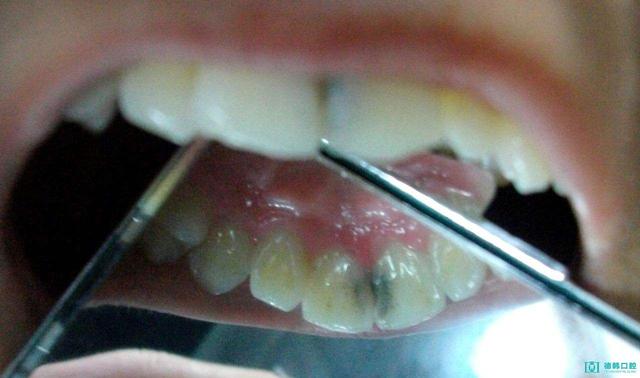

二、牙面黑渍

这是由外来的色素沉积附着引起的,我们 把它称为儿童"色素牙"。色素牙的黑斑呈点状、片状,主要聚集在牙颈部和牙体边缘,门牙尤为明显。